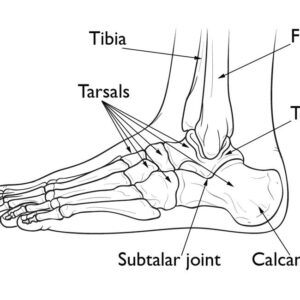

Foot & Ankle Patient informationPilon fractures are a distinct type of injury affecting the lower end of the tibia (shinbone), specifically involving the weight-bearing surface of the ankle joint. These fractures often extend to the fibula, the other bone in the lower leg. Typically resulting from high-impact incidents such as motor vehicle accidents or